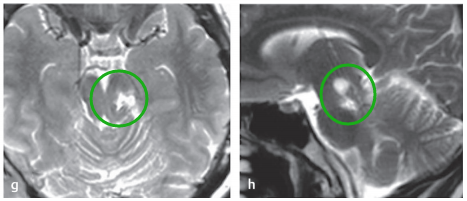

术后:手术无并发症,切口愈合良好(f)。术后患者神经功能完好,无新增缺损。患者预后良好,无神经功能缺损。组织病理学检查为1级毛细胞型星形细胞瘤。组织病理再次证实为WHOⅠ级毛细胞型星形细胞瘤。术后轴位(g)及矢状位(h)MRI证实肿瘤已全切。连续随访MRI显示,术后9年未见肿瘤复发。